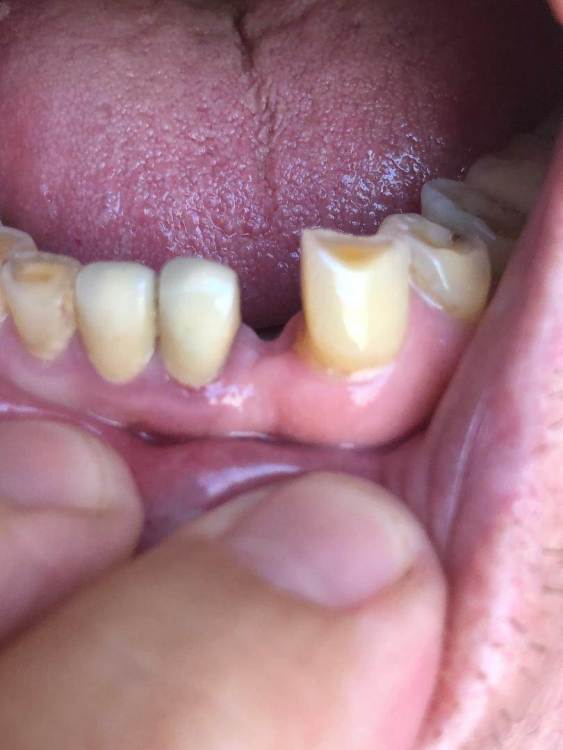

adent Опубликовано 1 апреля, 2021 Поделиться Опубликовано 1 апреля, 2021 Здравствуйте! Есть ли трудности какие либо или особенности для установки импланта (имплантата?) на место зуба №23. Мой врач имеет некоторые сомнения в успешности установки.Наращивание кости было в августе 2020 года. Возраст 79 лет. В целом здоровье мое без хронических заболеваний и аллергий. Есть ли риски какие после установки импланта через 3 дня делать длительный перелет? Спасибо! adent Ссылка на комментарий

red_butler Опубликовано 2 апреля, 2021 Поделиться Опубликовано 2 апреля, 2021 проблема как с местом для импланта (между корней ) так и для коронки 1 1 Ссылка на комментарий

kramer Опубликовано 2 апреля, 2021 Поделиться Опубликовано 2 апреля, 2021 Не влезет 1 Ссылка на комментарий